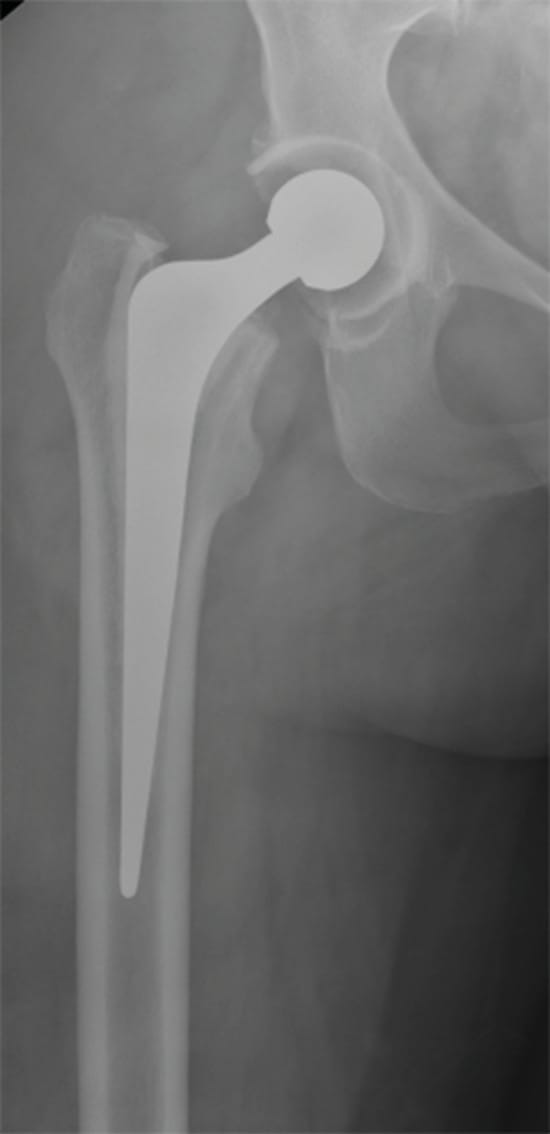

A 58-year-old woman consulted at our department with a history of high blood pressure, dyslipidemia and primary uncemented left total hip arthroplasty for osteoarthritis 9 months before, with a satisfactory result and a Harris Hip Score of 92 points. She presented walking without assistance complaining of right hip pain of 2 months duration. She referred dull pain, with an intensity of 5 on the visual analog scale and having received a steroid injection in the painful hip 6 weeks after the onset of symptoms and 15 days before consultation. Physical examination showed moderate pain during motion, with hip flexion 10 to 100°, internal rotation of 15° and external rotation of 20°. There was no fever or erythema in the area. At that time, an X-ray of both hips was performed which showed a normal right hip and left THA (Figure 1).

We therefore decided to perform open debridement, reaming the acetabular cavity and placing an articulated custom-made spacer coated with Vancomicyn loaded cement. Two grams of Vancomycin were added to each dose of 40 grams of cement. (Figure 5).